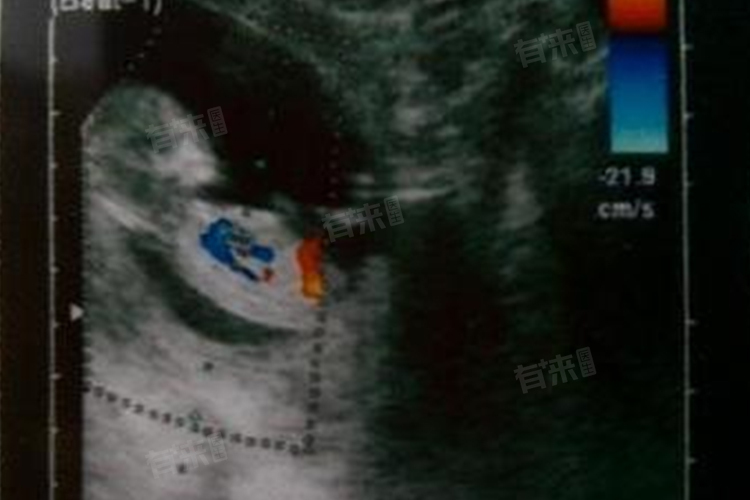

- 到了怀孕6-7周时,在妊娠囊内可以看到胎芽。胎芽是胚胎的雏形,此时已经开始有了初步的分化和发育,在超声图像上表现为一个小小的、具有一定形状的结构,其回声与妊娠囊内的液体也有所不同。并且在这个阶段,还能够检测到胎芽内的原始心管搏动。原始心管搏动是胚胎存活的关键标志,意味着胚胎已经开始有了血液循环系统的运作。超声仪器通过高频率的探头能够捕捉到心管微弱的跳动所产生的回声变化,并将其转化为可视化的图像,医生可以据此准确判断胚胎的发育状况。